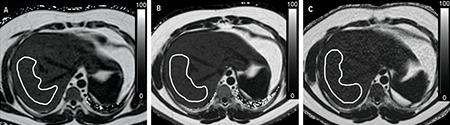

While comparing data from 24 patients who underwent three MR scans within a two-hour period, Andrew Trout, MD, and colleagues asked a basic question: Will MR scans produce similar results regardless of device manufacturer, field strength, and the reader who analyzed the results?

“These results show that technical differences are not a significant source of variability in proton density fat fraction (PDFF) measurements and suggest that MRI PDFF has promise technically as a biomarker for diagnosis and longitudinal imaging in fatty liver disease,” says Trout, the department’s Director of Clinical Research.

“MRI PDFF pulse sequences have significant advantages over biopsy, including the fact that they can cover large portions of the liver, providing a more global assessment of liver fat,” Trout explains.